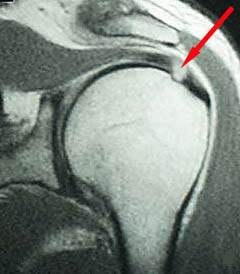

Normal Rotator Cuff MRI